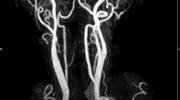

• Bauchgefäße

• Erfassung und Verlaufskontrolle bei arteriellen Aneurysmen (Aussackungen der Arterien), vor allem der Bauchaorta

• Darstellung von Gefäßengen an Nierenarterien, Baucharterien und Becken-/Beinarterien

MR-Angiografie (MRA)

• MR-Angiographie mit Kontrastmittel

• Erfassung arterieller und venöser Gefäße/Bypässe aller Körperregionen mit 3D-Rekonstruktion